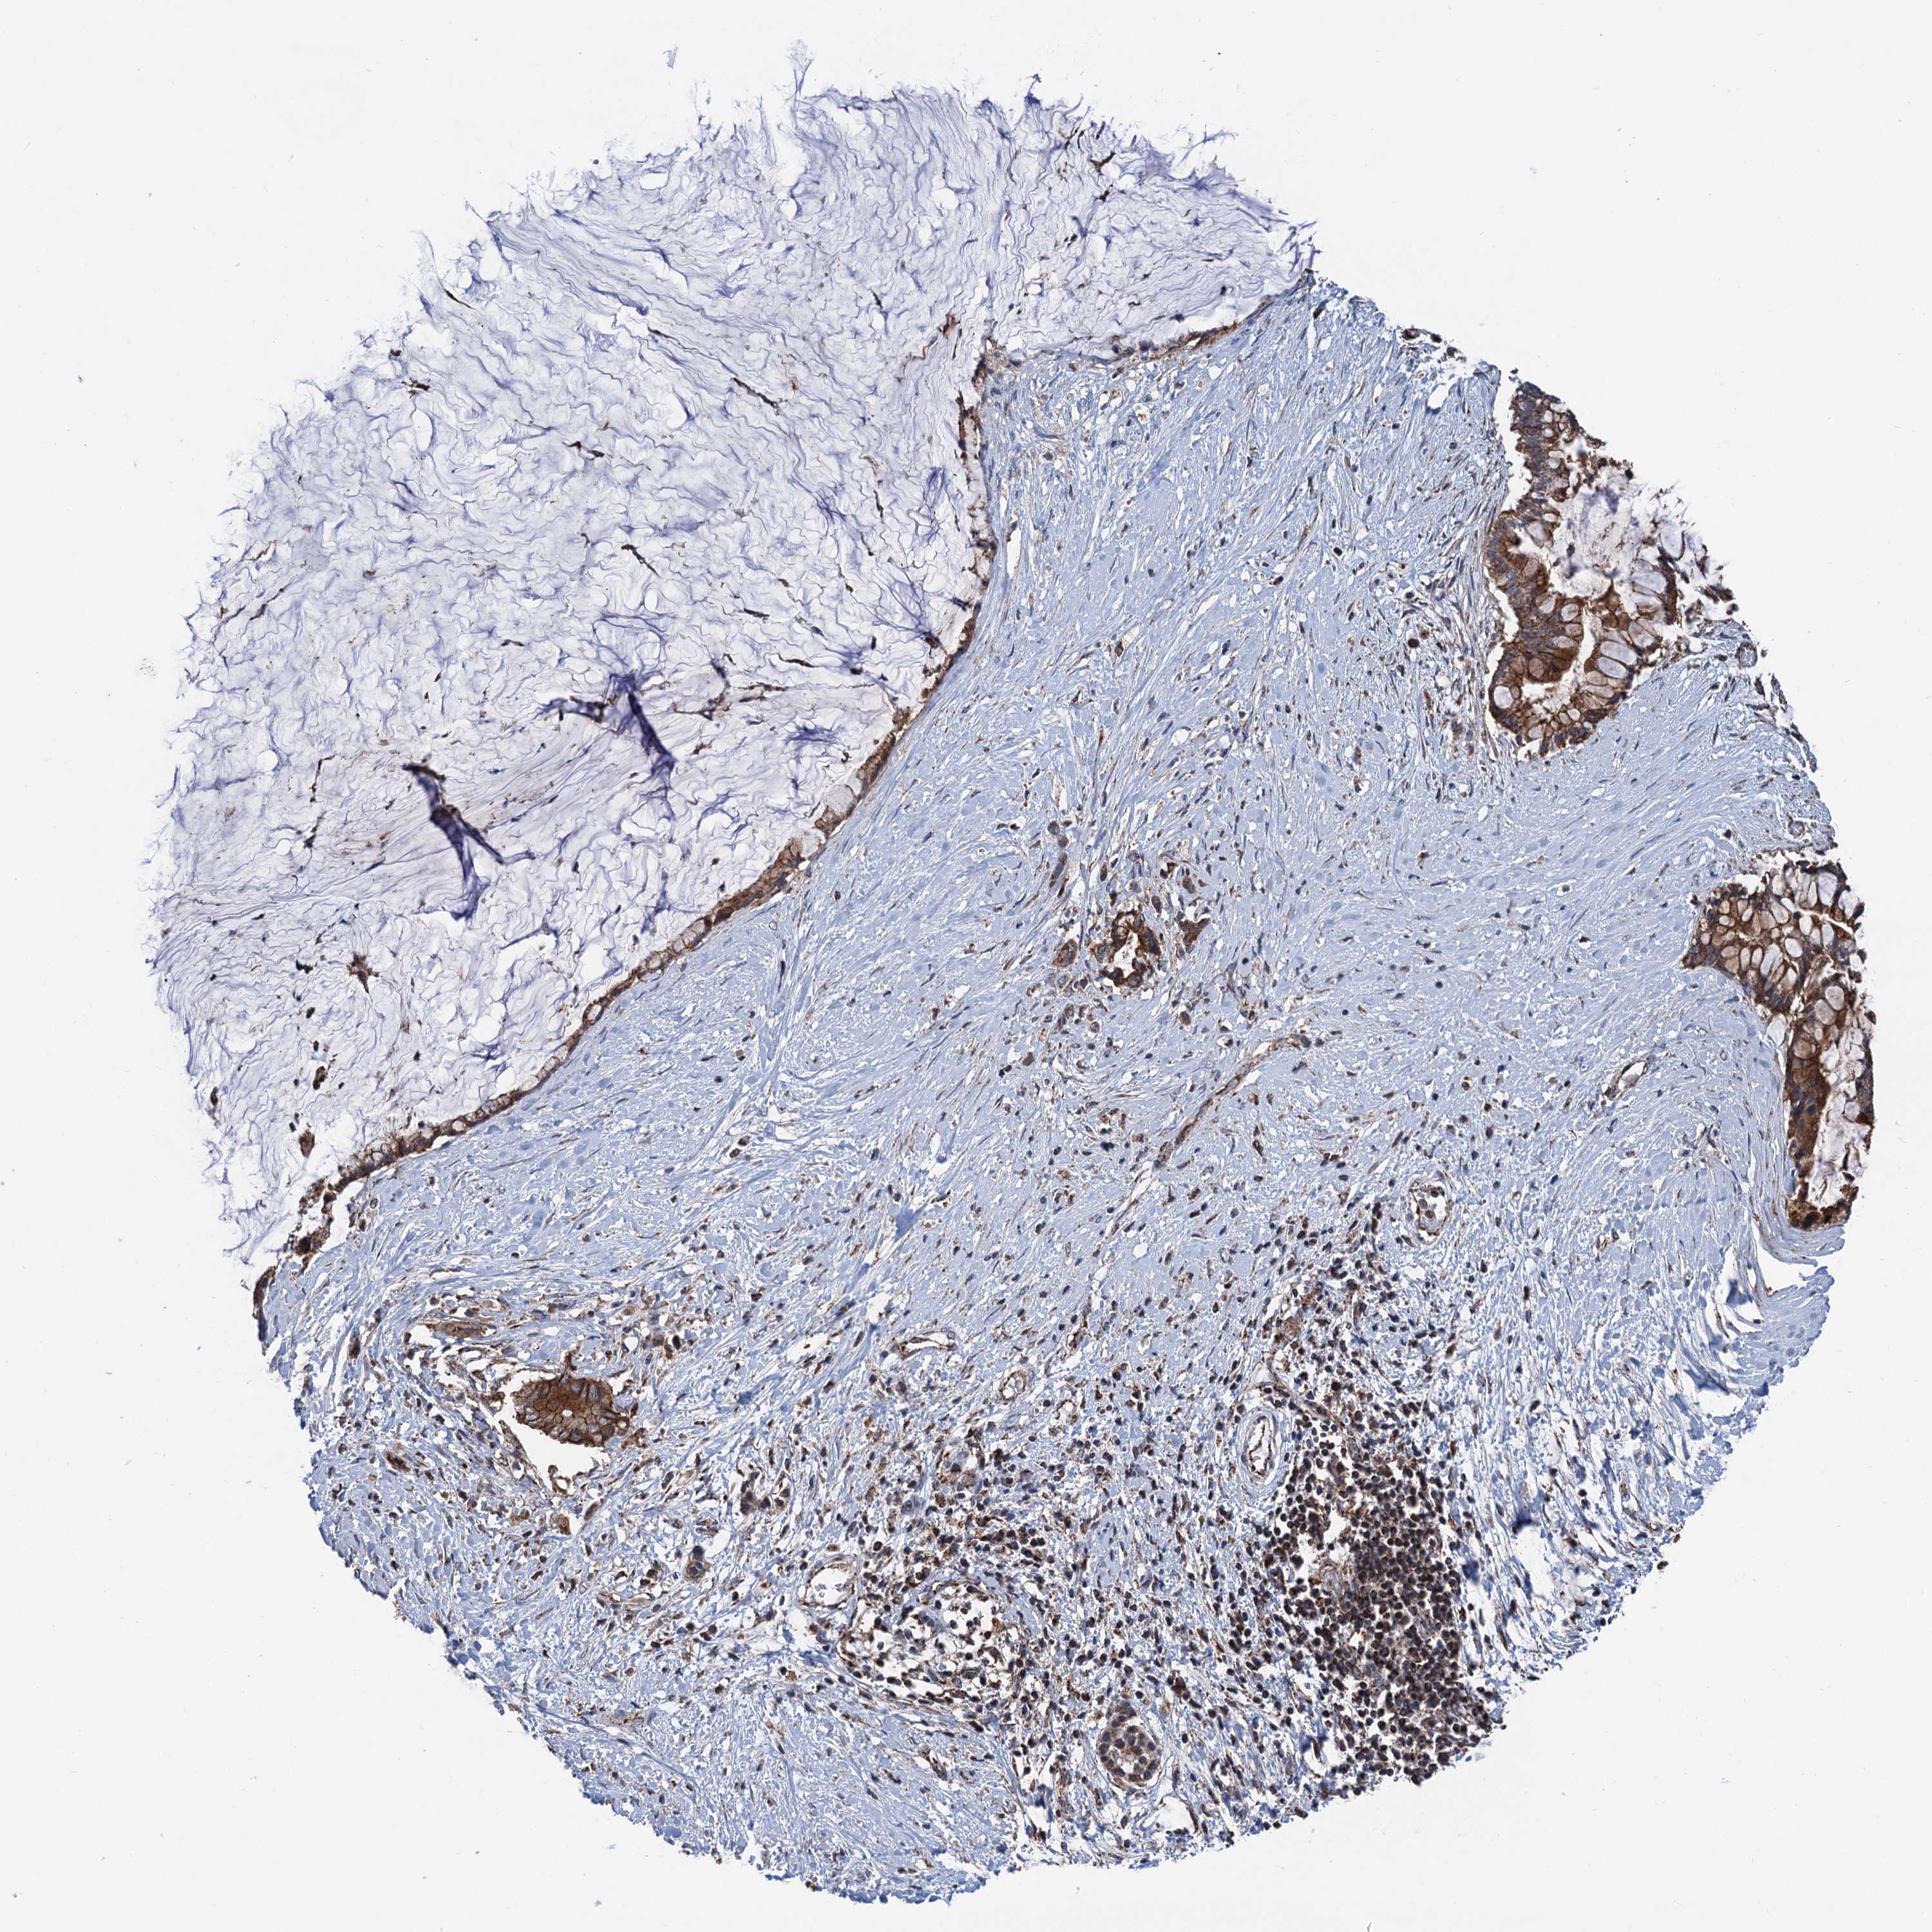

PANCREATIC CANCER - Protein expressioni

A mouse-over function shows sample information and annotation data. Click on an image to view it in a full screen mode. Samples can be filtered based on level of antibody staining by selecting one or several of the following categories: high, medium, low and not detected. The assay and annotation is described here.

Note that samples used for immunohistochemistry by the Human Protein Atlas do not correspond to samples in the TCGA dataset.

Antibody stainingi

Antibody staining in the annotated cell types in the current human tissue is reported as not detected, low, medium, or high, based on conventional immunohistochemistry profiling in selected tissues. This score is based on the combination of the staining intensity and fraction of stained cells.

Each image is clickable and will lead to virtual microscopy that enables deeper exploration of all samples and also displays staining intensity scores, fraction scores and subcellular localization as well as patient and tissue information for each sample.

Antibody HPA041423

Staining

High

Medium

Low

Not detected

Intensity

Strong

Moderate

Weak

Negative

Quantity

>75%

75%-25%

<25%

None

Location

Nuclear

Cytoplasmic/membranous

Cytoplasmic/membranous,nuclear

Adenocarcinoma, NOS